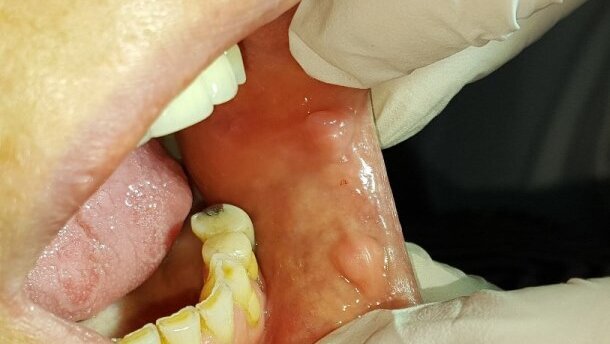

59-lernia pacjentka zgłosiła się do Zakładu Chirurgii Stomatologicznej WUM w celu leczenia zmian na błonie śluzowej jamy ustnej. W badaniu podmiotowym nie stwierdzono odchyleń. Pacjentka podaje pojawienie się zmian ok. 10 lat temu oraz zgłasza nawykowe nagryzanie błony śluzowej policzków.

W badaniu przedmiotowym wewnątrzustnym stwierdzono liczne braki zębowe, ostre krawędzie zębów, mnogie zmiany na błonie śluzowej policzków i kątów warg o charakterze włóknisto-przerostowym (fibroma), zmiany o średnicy 0,7-1,0 cm. Pacjentce zaproponowano usunięcie zmian za pomocą lasera CO2. Pacjentka wyraziła zgodę na zabieg.

W znieczuleniu nasiękowym 2% lignocainą z noradrenaliną (2 ml), wiązką promieniowania lasera CO2 o głębokości 0,2-0,25 mm usunięto zmienione patologicznie tkanki. Rany pooperacyjne pozostawiono do wygojenia przez ziarninowanie. Pacjentce zalecono Solcoseryl Dental do stosowania w celu zabezpieczenia ran pooperacyjnych, dietę miękką oraz wzmożoną higienę jamy ustnej. Badanie histopatologiczne potwierdziło rozpoznanie kliniczne.